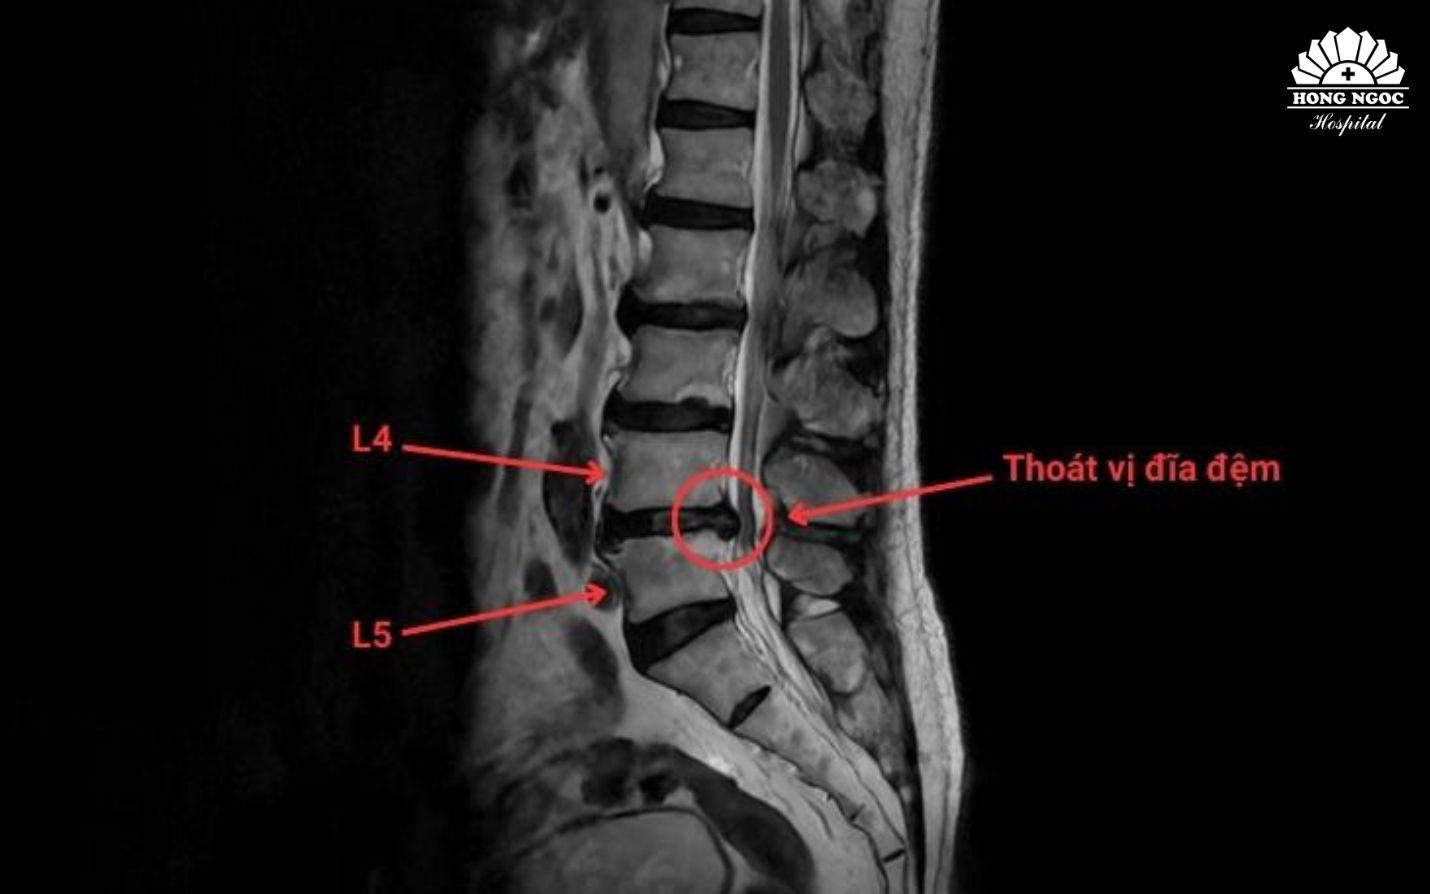

Phim chụp thoát vị đĩa đệm cột sống thắt lưng L4/L5

Hay trường hợp của bệnh nhân Q (63 tuổi) bị đau lưng mạn tính do thoát vị đĩa đệm chèn ép rễ thần kinh tại vị trí L4/L5 khiến bệnh nhân phải ngủ trong tư thế quỳ. Đặc biệt, gần đây bệnh nhân gặp tình trạng tê bì, yếu chi, đi lại khó khăn. Khi các phương pháp điều trị nội khoa không đáp ứng, bệnh nhân được chỉ định thăm khám và can thiệp chuyên sâu.